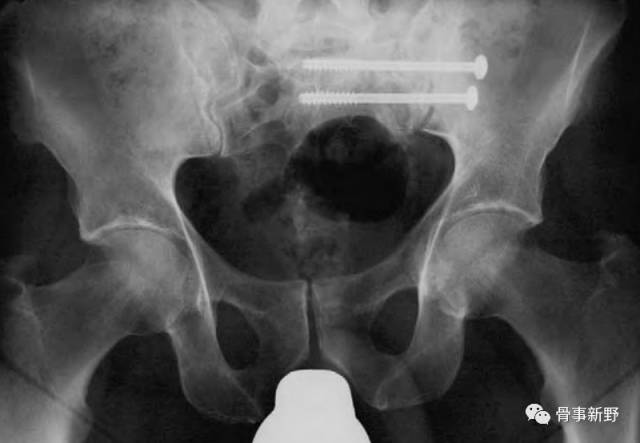

垂直不稳(术前)

垂直不稳复位、固定(术后)

垂直不稳再移位、螺钉扭曲(术后)

通过置入第二枚螺钉,或与其它固定方式组合,构成三角固定,可明显增加后环稳定性。